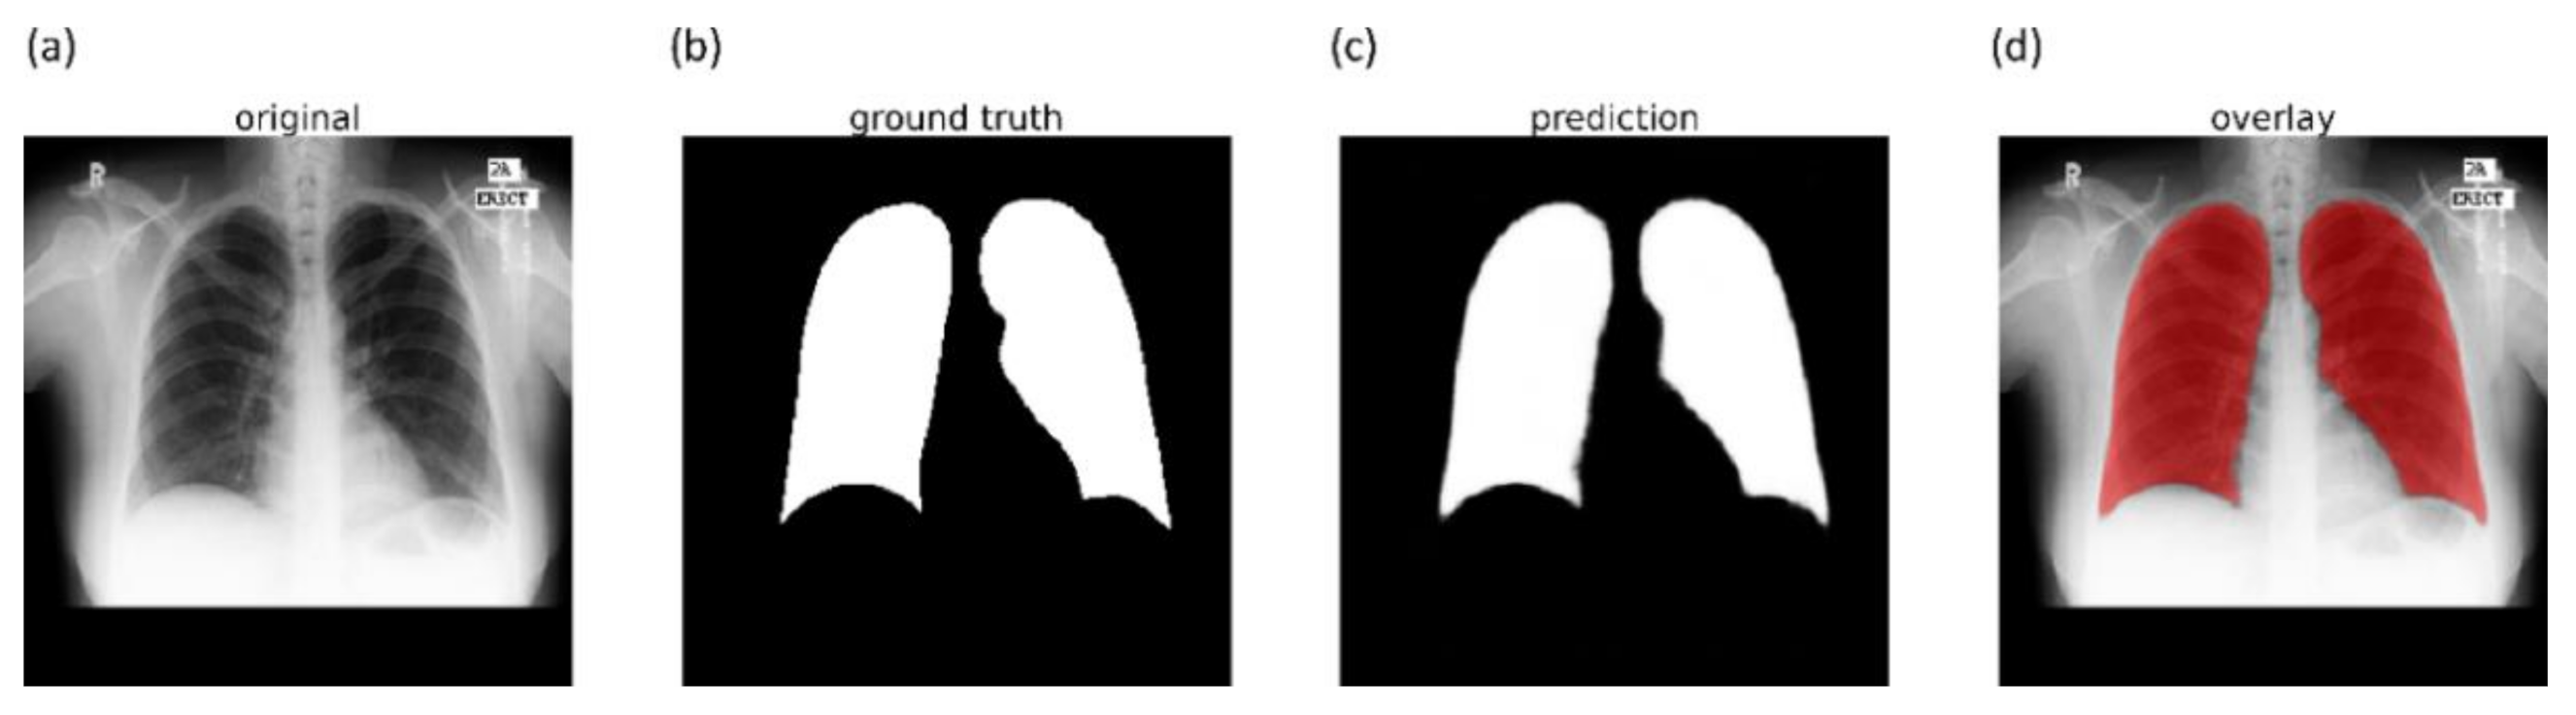

2.4. Lung Segmentation and Preprocessing

The performance of DL models is severely impacted by data quality. Irrelevant features may lead to biased learning and suboptimal model performance. The task of detecting TB or other pulmonary disease manifestations is confined to the lung regions. Thus, regions in CXRs other than the lungs are irrelevant to be learned by the models. Hence, it is crucial to segment the lung regions and train the lung ROI models to help them learn relevant features concerning normal lungs or other pulmonary manifestations.

The U-Nets are one of the most powerful CNN models that are used for precise and accurate segmentation of medical images [

20]. The principal advantage of U-Net is that it can handle data scarcity and learn from small training sets. The U-Net has a U-shaped architecture. It is composed of an encoder/contracting path and a decoder/expanding path and performs pixelwise class segmentations. The feature maps from the encoder’s various levels are passed over to the decoder to predict features at varying scales and complexities.

In this study, we propose CXR modality-specific VGG-16 and VGG-19 U-Nets, referred to as VGG-16-CXR-U-Net and VGG-19-CXR-U-Net models. These models use the CXR modality-specific pretrained VGG-16 and VGG-19 models from

Section 2.3 as the encoder backbone. The architecture of the VGG-16-CXR-U-Net and VGG-19-CXR-U-Net models are shown in

Figure 3. The encoder of the VGG-16-CXR-U-Net and VGG-19-CXR-U-Net models are each made up of five convolutional blocks, consisting of 13 and 16 convolutional layers, respectively, following the original VGG-16 and VGG-19 architecture. The green downward arrow at the bottom of each convolutional block in the encoder designates a max-pooling operation (2 × 2 filters, 2 strides) to reduce image dimensions. The decoder of the VGG-16-CXR-U-Net and VGG-19-CXR-U-Net models comprises five convolutional blocks and consists of 15 convolutional layers. The upward red arrow at the top of each convolutional block in the decoder signifies an upsampling operation that performs transposed convolutions to restore the image to its original dimensions. Each convolutional layer in the encoder and decoder is followed by batch normalization (BN) and ReLU activation. The pink arrow signifies skip-connections that combine the corresponding feature maps and restores the original image dimensions. Sigmoidal activation is used at the final convolutional layer to predict binary pixel values.

We evaluated the segmentation performance of the VGG-16-CXR-U-Net and VGG-19-CXR-U-Net models and other SOTA U-Net variants, including the standard U-Net, V-Net with ResNet blocks, improved attention U-Net, ImageNet-pretrained VGG-16 U-Net, and VGG-19-U-Net toward lung segmentation.

Figure 4 illustrates the lung segmentation workflow.